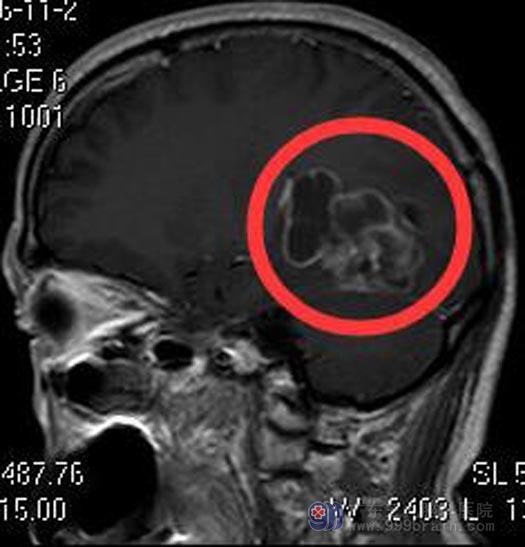

徐先生5天前突发晕厥,无明显头痛头晕、四肢抽搐等不适,时间约2-3分钟,当地医院头颅CT提示“左侧枕叶、丘脑多发占位”;广东三九脑科医院头颅MR提示:左侧枕叶-侧脑室三角区示一不规则形占位性病变,5.6cm×3.9cm×4.1cm,考虑高级别肿瘤性病变,胶质母细胞瘤或间变室管膜瘤可能,待排转移瘤。